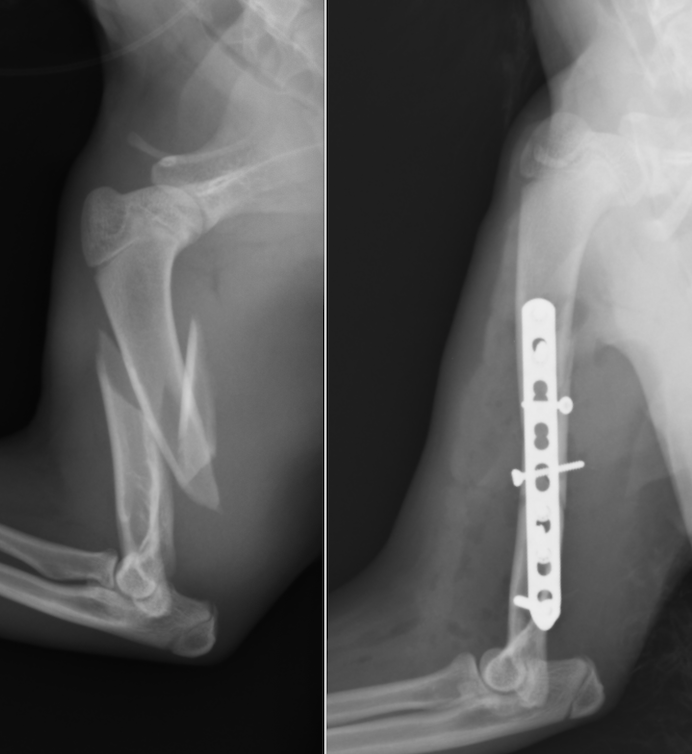

上腕骨粉砕骨折した猫

犬猫では上腕骨の骨折は比較的稀な疾患です。猫の上腕骨は捻りの力が強く発生するのと外固定が困難であるため第Ⅰ選択の治療がプレートスクリュー固定となります。固定強度が弱い場合には髄内ピンをプラスすることもあります。

今回の症例は5ヶ月の上腕骨粉砕骨折です。粉砕している場合骨片をうまく合わせることができれば固定強度が強くなります。粉砕している骨が小さすぎたり、合わせることが困難な場合には固定強度が著しく低下するため髄内ピンなどを追加します。

この症例の場合粉砕骨片をラグスクリュー法という方法である程度合わせることができたのですが、一部欠損が合ったためロッキングプレートという強度の高いプレートを使用しました。

術後の経過は順調で癒合した段階でプレート抜去を行い、問題なく経過しています。